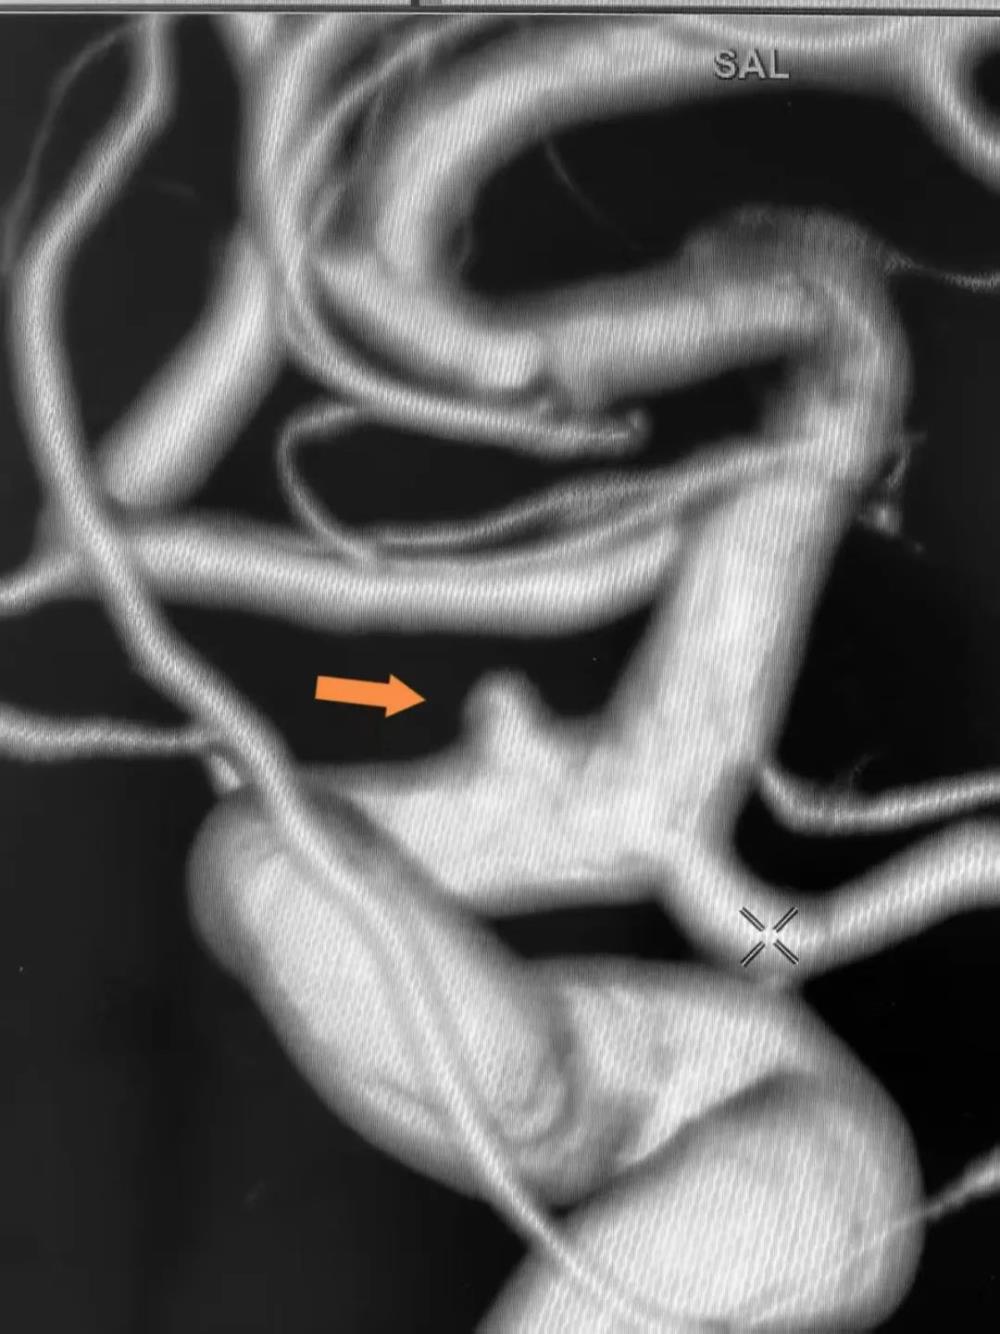

术前三维造影

在肾病内科协助制定肾功能保护方案后,紧急完成全脑血管造影,确诊为"左侧颈内动脉眼动脉段血泡样动脉瘤"。因该类动脉瘤形态特殊,传统开颅夹闭难度大,而常规介入栓塞易复发且术中易破裂,纪文军主任医师凭借丰富的经验和对前沿技术的掌握,最终决定采用国内领先的"密网支架(血流导向装置)联合弹簧圈栓塞"术。

术中,通过微导管精准塑形、支架完美释放,实现动脉瘤致密栓塞。术后,造影显示动脉瘤完全消失,载瘤动脉及分支血管血流通畅,患者无神经功能缺损,安返病房。